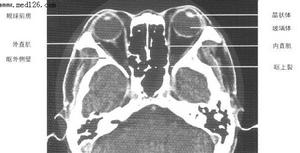

6、在B型超音波圖及CT片上可見到增粗的眼外肌或無邊界的增殖性組織。假瘤或在肌錐內,或在肌錐外。

4、在B型超音波圖及CT片上可見到增粗的眼外肌或無邊界的增殖性組織。假瘤或在肌錐內,或在肌錐外。

正常眼眶CT圖多採用廣譜抗生素(青黴素、先鋒黴素、克林黴素)合併皮質類固醇聯合治療,特別是以漿細胞為主者效果最好,早期病例往往可以獲得明顯緩解好轉。